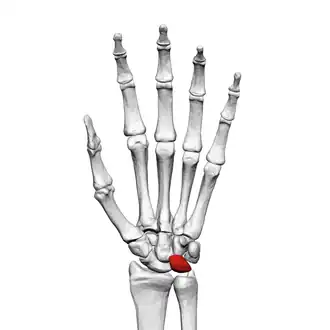

![]() Left hand anterior view (palmar view). Lunate bone shown in red. | |

The lunate bone (semilunar bone) is a carpal bone in the human hand. It is distinguished by its deep concavity and crescentic outline. It is situated in the center of the proximal row carpal bones, which lie between the ulna and radius and the hand. The lunate carpal bone is situated between the lateral scaphoid bone and medial triquetral bone.

The lunate is a crescent-shaped carpal bone found within the hand. The lunate is found within the proximal row of carpal bones. Proximally, it abuts the radius. Laterally, it articulates with the scaphoid bone, medially with the triquetral bone, and distally with the capitate bone. The lunate also articulates on its distal and medial surface with the hamate bone.[2]: 708 [3]

Lunate bone of the left hand (shown in red). Animation. -